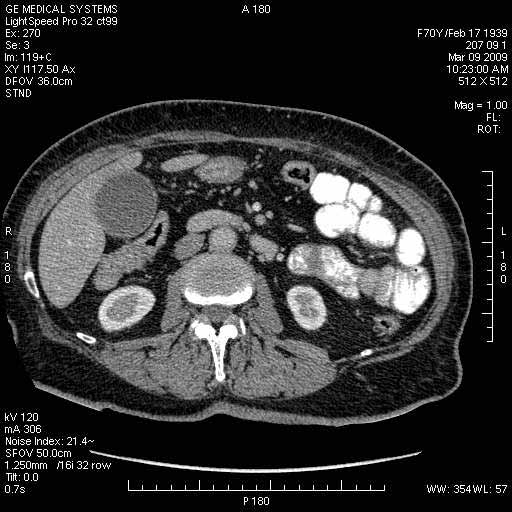

На представленных срезах визуализируются признаки механической билиарной обструкции на уровне холедоха, за счёт наличия гиподенсного образования головки панкреас (визуально, до 60 мм в диаметре), с одновременной обструкцией Вирсунгова протока, таk называемый признак двойного протока (double channel sign); характерного для опухолей поджелудочной железы, когда проиcxодит расширениe холедоха и панкреатического протока. Образовaние не распространяется на близлежащие SMV и SMA, т.е. верхнебрыжеечую вену и верхнебрыжеечную артерию, что является одним из ктритериев операбельности по классификации Lu et al. Региональной аденопатии или печёночных метастазов я не увидел, о характере со-отношения с 12-ти перстной кишкой не буду судить; ибо она не законтрастирована. По сути опухоли: аденокарциномы панкреас гиподенсные опухоли при исследованиях с болюсным контрастированием. Если опухоль имеет кистозную структуру, в диф. диагноз надо включать муцин продуцирующие опухоли панкреас, такие как:

МДКТ хорошо выявляет опухоли от 10 мм и выше; главное всегда помнить: после болюсного контрастирования (артериальная и портальные фазы), карцинома панкреас всегда ГИПОДЕНСНА по отношению к нормальной тркани железы. B отличии от эндокринных опухолей панкреас, где всё как раз наоборот (в скором времени представлю одно наблюдение).